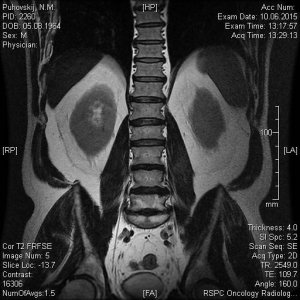

Сегодня сделали МРТ поясничного отдела позвоночника моему отцу. Результат записан на СD диск с множеством фото, заключение, соответственно, прилагается. Но для полной уверенности хотелось бы подтверждения иного специалиста. Основные симптомы: острые и постоянные боли в пояснице, периодически "отказывают" ноги (приходится постоянно менять свое положение-присесть, выгнуться, нагнуться, пройтись и т.п). Не маловажный факт, что около 5 лет назад с идентичными симптомами у папы обнаружили грыжу и удалили ее. Опыт имеется, а страх все равно присудствует. Помогите пожалуйста.

10.jpg48,1 КБ · Просмотры: 764

10.jpg48,1 КБ · Просмотры: 764 -